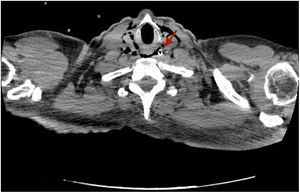

Varón de 46 años, con historia de múltitiples intervenciones abdominales, ingresado por oclusión intestinal. Se coloca sonda nasogástrica (SNG) que inicialmente no es productiva. Se solicita tomografía tóraco-abdominal por empeoramiento clínico, observándose un trayecto extraluminal de la SNG a nivel abdominal y torácico (fig. 1) sin hallar punto de perforación, y que se orienta como probable perforación a nivel cervical (fig. 2). La exploracion ORL identifica la perforación en cavum inferior, disecando la pared posterior de la faringe. Se retira la SNG, y se inicia tratamiento médico con corticoides, fluconazol y meropenem. El paciente presenta mejoría clínica radiológica e inicia tolerancia oral a la semana.